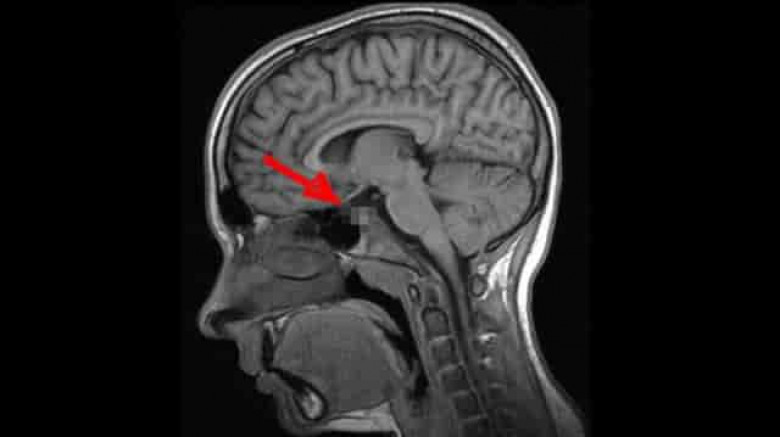

Գիտնականները հայտարարել են, որ ուղեղի այս հիվանդությամբ տառապում է մարդկանց գերակշիռ մեծամասնությունը.

Դեժավյուն հոգեբանական կարգավիճակ է, որի ընթացքում մարդուն թվում է, թե նա էլի է հայտնվել նման իրավիճակում: Երևի Ձեզ հետ էլ է պատահել նման բան՝ որևէ անծանոթ տուն կամ վայր առաջին անգամ եք ոտք դրել, սակայն Ձեզ թվացել է, որ այդտեղ արդեն եղել եք:

2009 թ. գիտնականները որոշեցին լրջորեն ուսումնասիրել այս ոչ սովորական երևույթը: Որոշ ժամանակ անց Մասաչուսեթսի տեխնոլոգիական համալսարանի մասնագետները հայտարարեցին, որ ուղեղն ունի այնպսիս հատված, որը պատասխանատու է այս երևույթի համար: Դեժավյուի գլխավոր դերը այն նեյրոններինն է, որոնց շնորհիվ կարողանում ենք զգալ պատկերների ամենափոքր տարբերություններն անգամ: Սրա շնորհիվ մարդը գիտակցում է, թե ինչպիսի տպավորություններ է ինքը վաղուց արդեն ստացել, իսկ որոնք են ամբողջապես նոր նրա համար: Այսն կարծես մարդու «կյանքի փորձառությունը» բաժանում է անցյալի և ներկայի: Սակայն երբ երկու տպավորություններ իրար շատ նման են լինում, ուղեղի այդ հատվածի աշխատանքը «կախում է», ինչն էլ բերում է տարօրինակ այս զագցմանը:

2009թ. բացահայտումից հետո միայն մեկ անպատասխան հարց է մնացել՝ այս երևույթը բնորոշ է առողջ մարդկա՞նց, թե՞ ոչ այնքան: Պատասխանը գտնելու պատասխանատվությունն իրենց վրա վերցրին Չեխիայի Մասարիկա և Մեծ Բրիտանիայի Էկսետերի համալսարանների մասնագետները: Նրանք պարզեցին, որ դեժավյու կարող է լինել անգամ փոքր տարիքում, երբ նոր կազմավորվում է ուղեղը: Հոգնախության և սթրեսի ժամանակ ուղեղի տվյալ հատվածի աշխատանքը խաթարվում է և արդյունքում առաջանում են հիշողություններ այնպիսի բաների մասին, որոնք երբեք չեն էլ եղել: Գիտնականների վերջնական դիագնոզը ցավալի է՝ դեժավյուն համարվում է նյարդաբանական խանգարում: